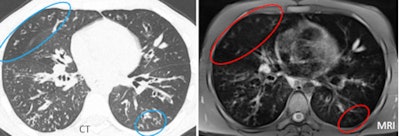

![]() |

| MRI often overestimated mild disease, as in the case of a 24-year-old male patient with mild cystic fibrosis. In this patient, some small bronchiectasis of the right upper lobe (CT, left) appeared as a large area of mucus plugging (at MRI, right), resulting in an overestimation of the mucus score. This occurred because the wall thickening was blurred in the MR image, mimicking mucus plugs. |